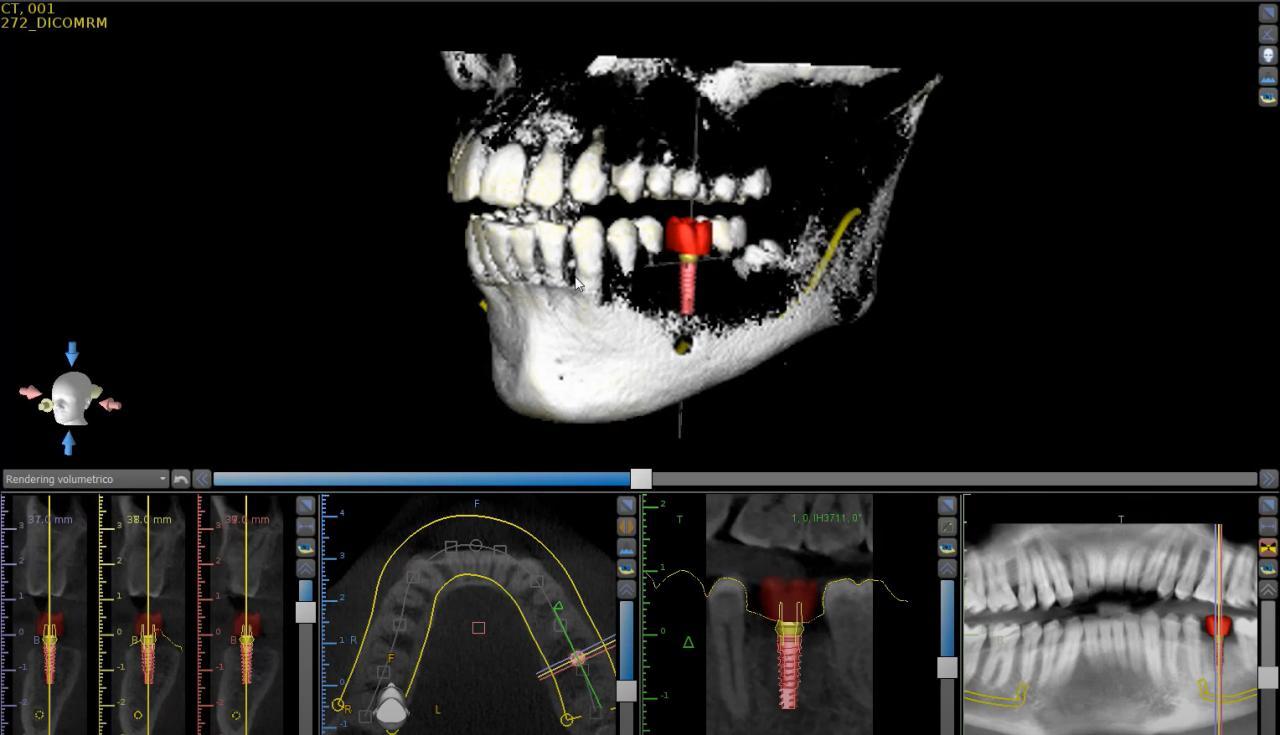

Chirurgia e Implantologia

L'implantologia è una branca della chirurgia odontoiatrica che permette di ripristinare il sorriso dei pazienti che hanno perso uno o più denti. Essa si avvale dell'impianto di denti fissi in modo semplice, sicuro e duraturo nel tempo.

Utilizziamo le più moderne tecnologie,con la chirurgia computer assistita per offrire ai nostri pazienti più precisione e meno traumi. Ci prenderemo cura di te in modo da ricostruire il tuo sorriso.

La Cone Beam 3D è una moderna metodologia diagnostica che consente di riprodurre sezioni o un'immagine del cranio tridimensionale che viene utilizzata, in genere, per l'implantologia.